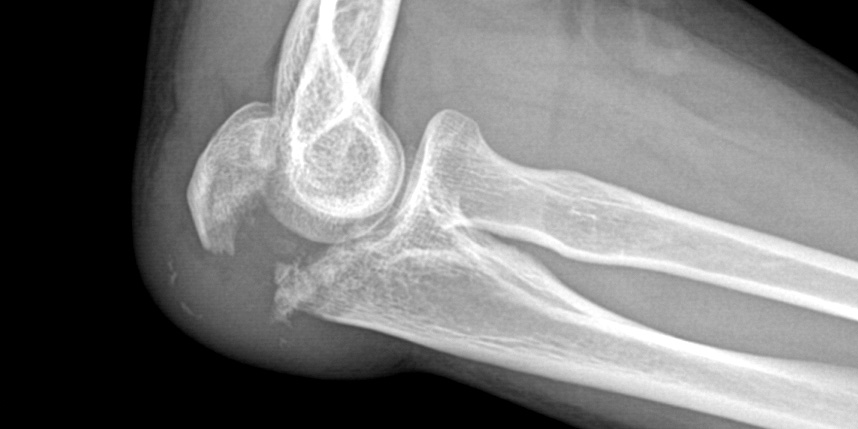

무릎 골절